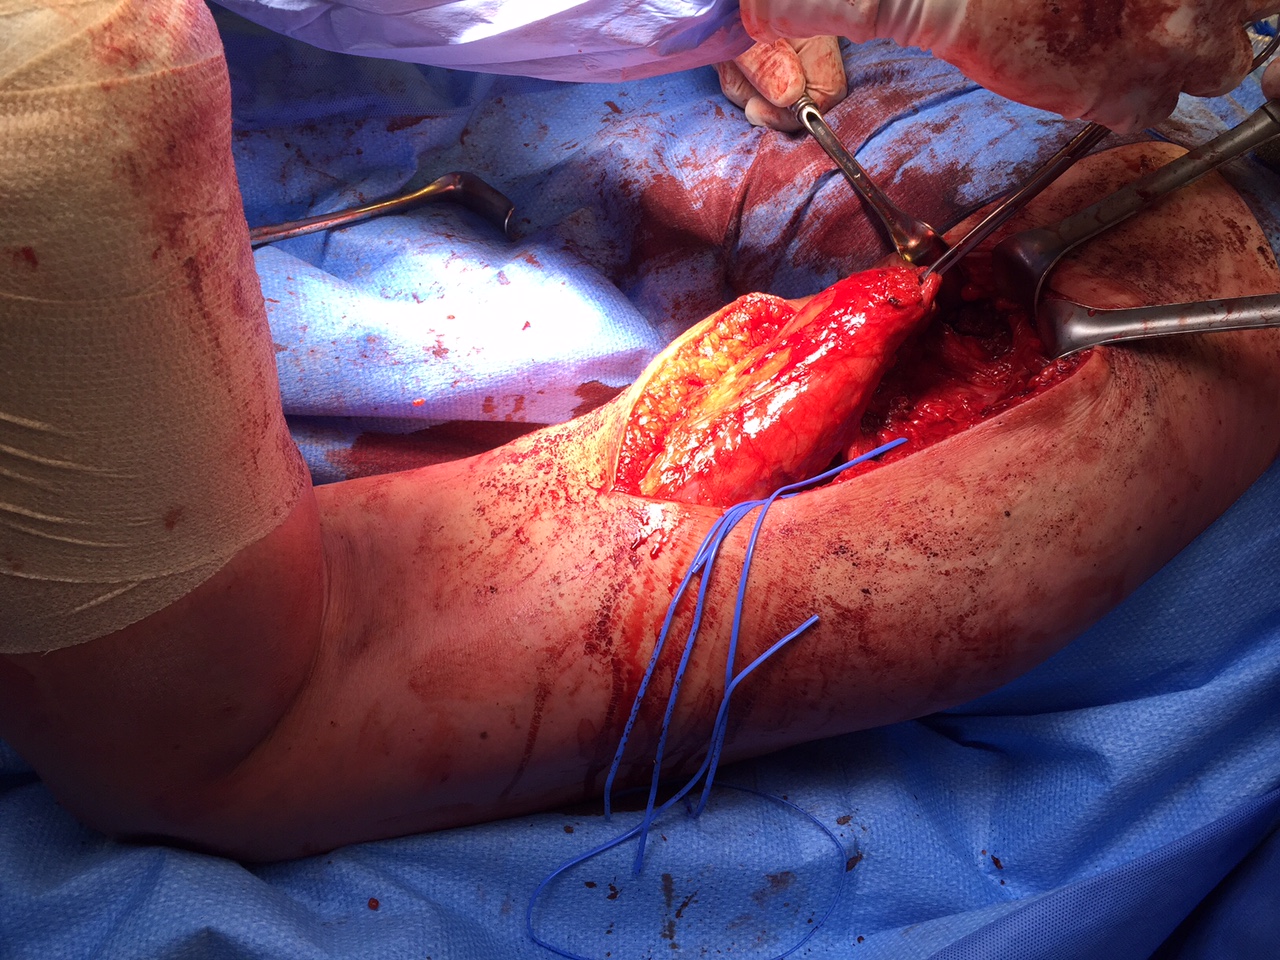

Deep dissection

- identify and preserve sciatic nerve (lateral to hamstring)

Hamstring (*) with sciatic nerve lateral to hamstring (blue vessiloop)

Identify and release proximal hamstring tendon

Stump of the conjoint tendon (*)